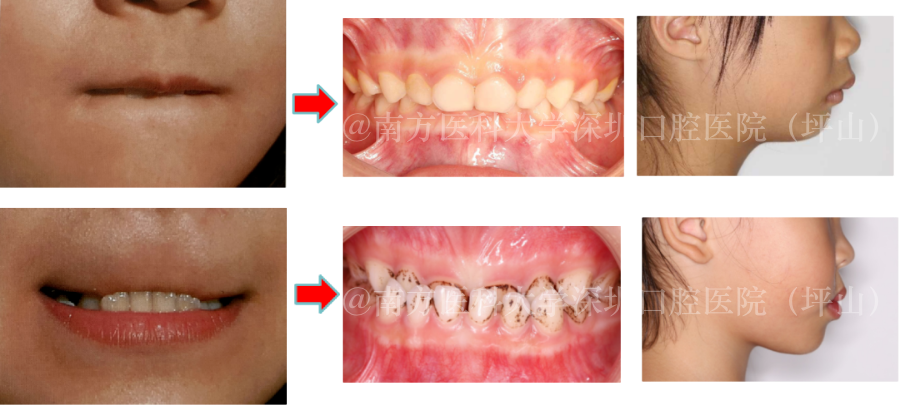

▲严重反𬌗患者

(下颌骨矢状劈开手术+正畸联合治疗)

▲双颌前突患者

(上下颌骨分段截骨术+正畸联合治疗)